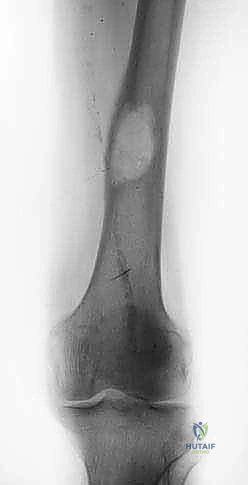

FIG 2 • Conventional radiograph. A,B. Lateral view with and without correction of the forefoot equinus. (continued)*

Lateral view (standing) (FIG 2A) Posterior shift of the lateral malleolus

The longitudinal axis of the talus is parallel to the axis of the calcaneus.

The calcaneus seems to be shortened due to varus position.

There is decreased distance between the navicular and the medial malleolus.

The calcaneocuboid joint is visible; it is normally obscured by the talonavicular joint. The first metatarsal is plantarflexed and its head has a plantar prominence.

Claw toes

The posterior subtalar joint is projected horizontally. Opened sinus tarsi (“sinus tarsi window”)

Anteroposterior (AP) view (standing) (FIG 2B)

Longitudinal axes of the talus and calcaneus are parallel.

There is a medial shift of the talonavicular joint and, in some cases, the calcaneocuboid joint. The first metatarsal seems to be shortened due to its plantarflexed position.

There is overlapping of the metatarsal bones, especially the fourth and fifth.

AP view of the ankle joint (standing) (FIG 2C) Varus deformity of the ankle joint

Hindfoot varus